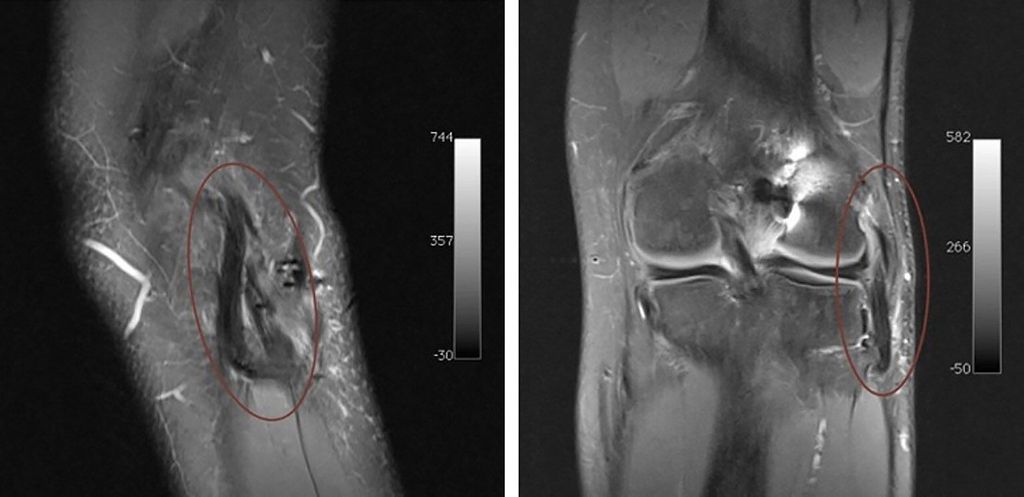

Aus unserer täglichen Praxis möchten wir den Fall eines 25-jährigen professionellen Fußballspielers vorstellen. Der Patient hatte sich während eines Spiels im Rahmen eines Hyperextensionstraumas eine vordere Kreuzbandruptur mit einer lateralen Seitenbandruptur zugezogen. Zusätzlich zeigten sich eine distale Partialruptur des M. biceps femoris und eine Teilruptur des M. popliteus (Abb.2). Die operative Versorgung erfolgte 14 Tage nach dem Trauma. Das vordere Kreuzband wurde mit einem BTB(Bone-Tendon-Bone-)Patellarsehnentransplantat, welches mit 2 Schrauben fixiert wurde, rekonstruiert. Intraoperativ zeigte sich, wie erwartet, eine vermehrte laterale Aufklappbarkeit unter Varusstress bei intakter Popliteussehne. Aufgrund der Begleitverletzung des M. biceps femoris wurde ein offener Zugang gewählt. Es wurde ein bogenförmiger lateraler Hautschnitt im Sinne einer „hockey stick incision“ angewandt und die laterale Gelenksecke sowie der N. peroneus dargestellt (Abb.3). Es zeigte sich die Sehne des M. biceps femoris am fibularen Ansatz handschuhförmig ausgerissen und das laterale Seitenband rupturiert. Es wurde die posterolaterale Gelenksecke mit einem Semitendinosustransplantat in Larson-Technik rekonstruiert und die Sehne des M. biceps femoris am fibularen Ansatz mit Fiberwire-Fäden transossär refixiert. Postoperativ wurde der Patient mit einer Knieorthese für 6 Wochen sowie Teilbelastung in den ersten 4 Wochen mobilisiert. In den ersten 2 Wochen erfolgte zusätzlich eine passive Mobilisierung mittels einer Motorschiene bis maximal 60°-Flexion.

Abb. 3: Bogenförmiger lateraler Hautschnitt („hockey stick incision“) zur Darstellung der posterolateralen Gelenksecke und des N. peroneus